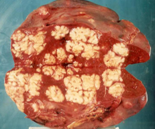

Multiple hepatic abscesses in other patients with cholecystocolic fistulas (Courtesy Dr. V. Penopoulos)